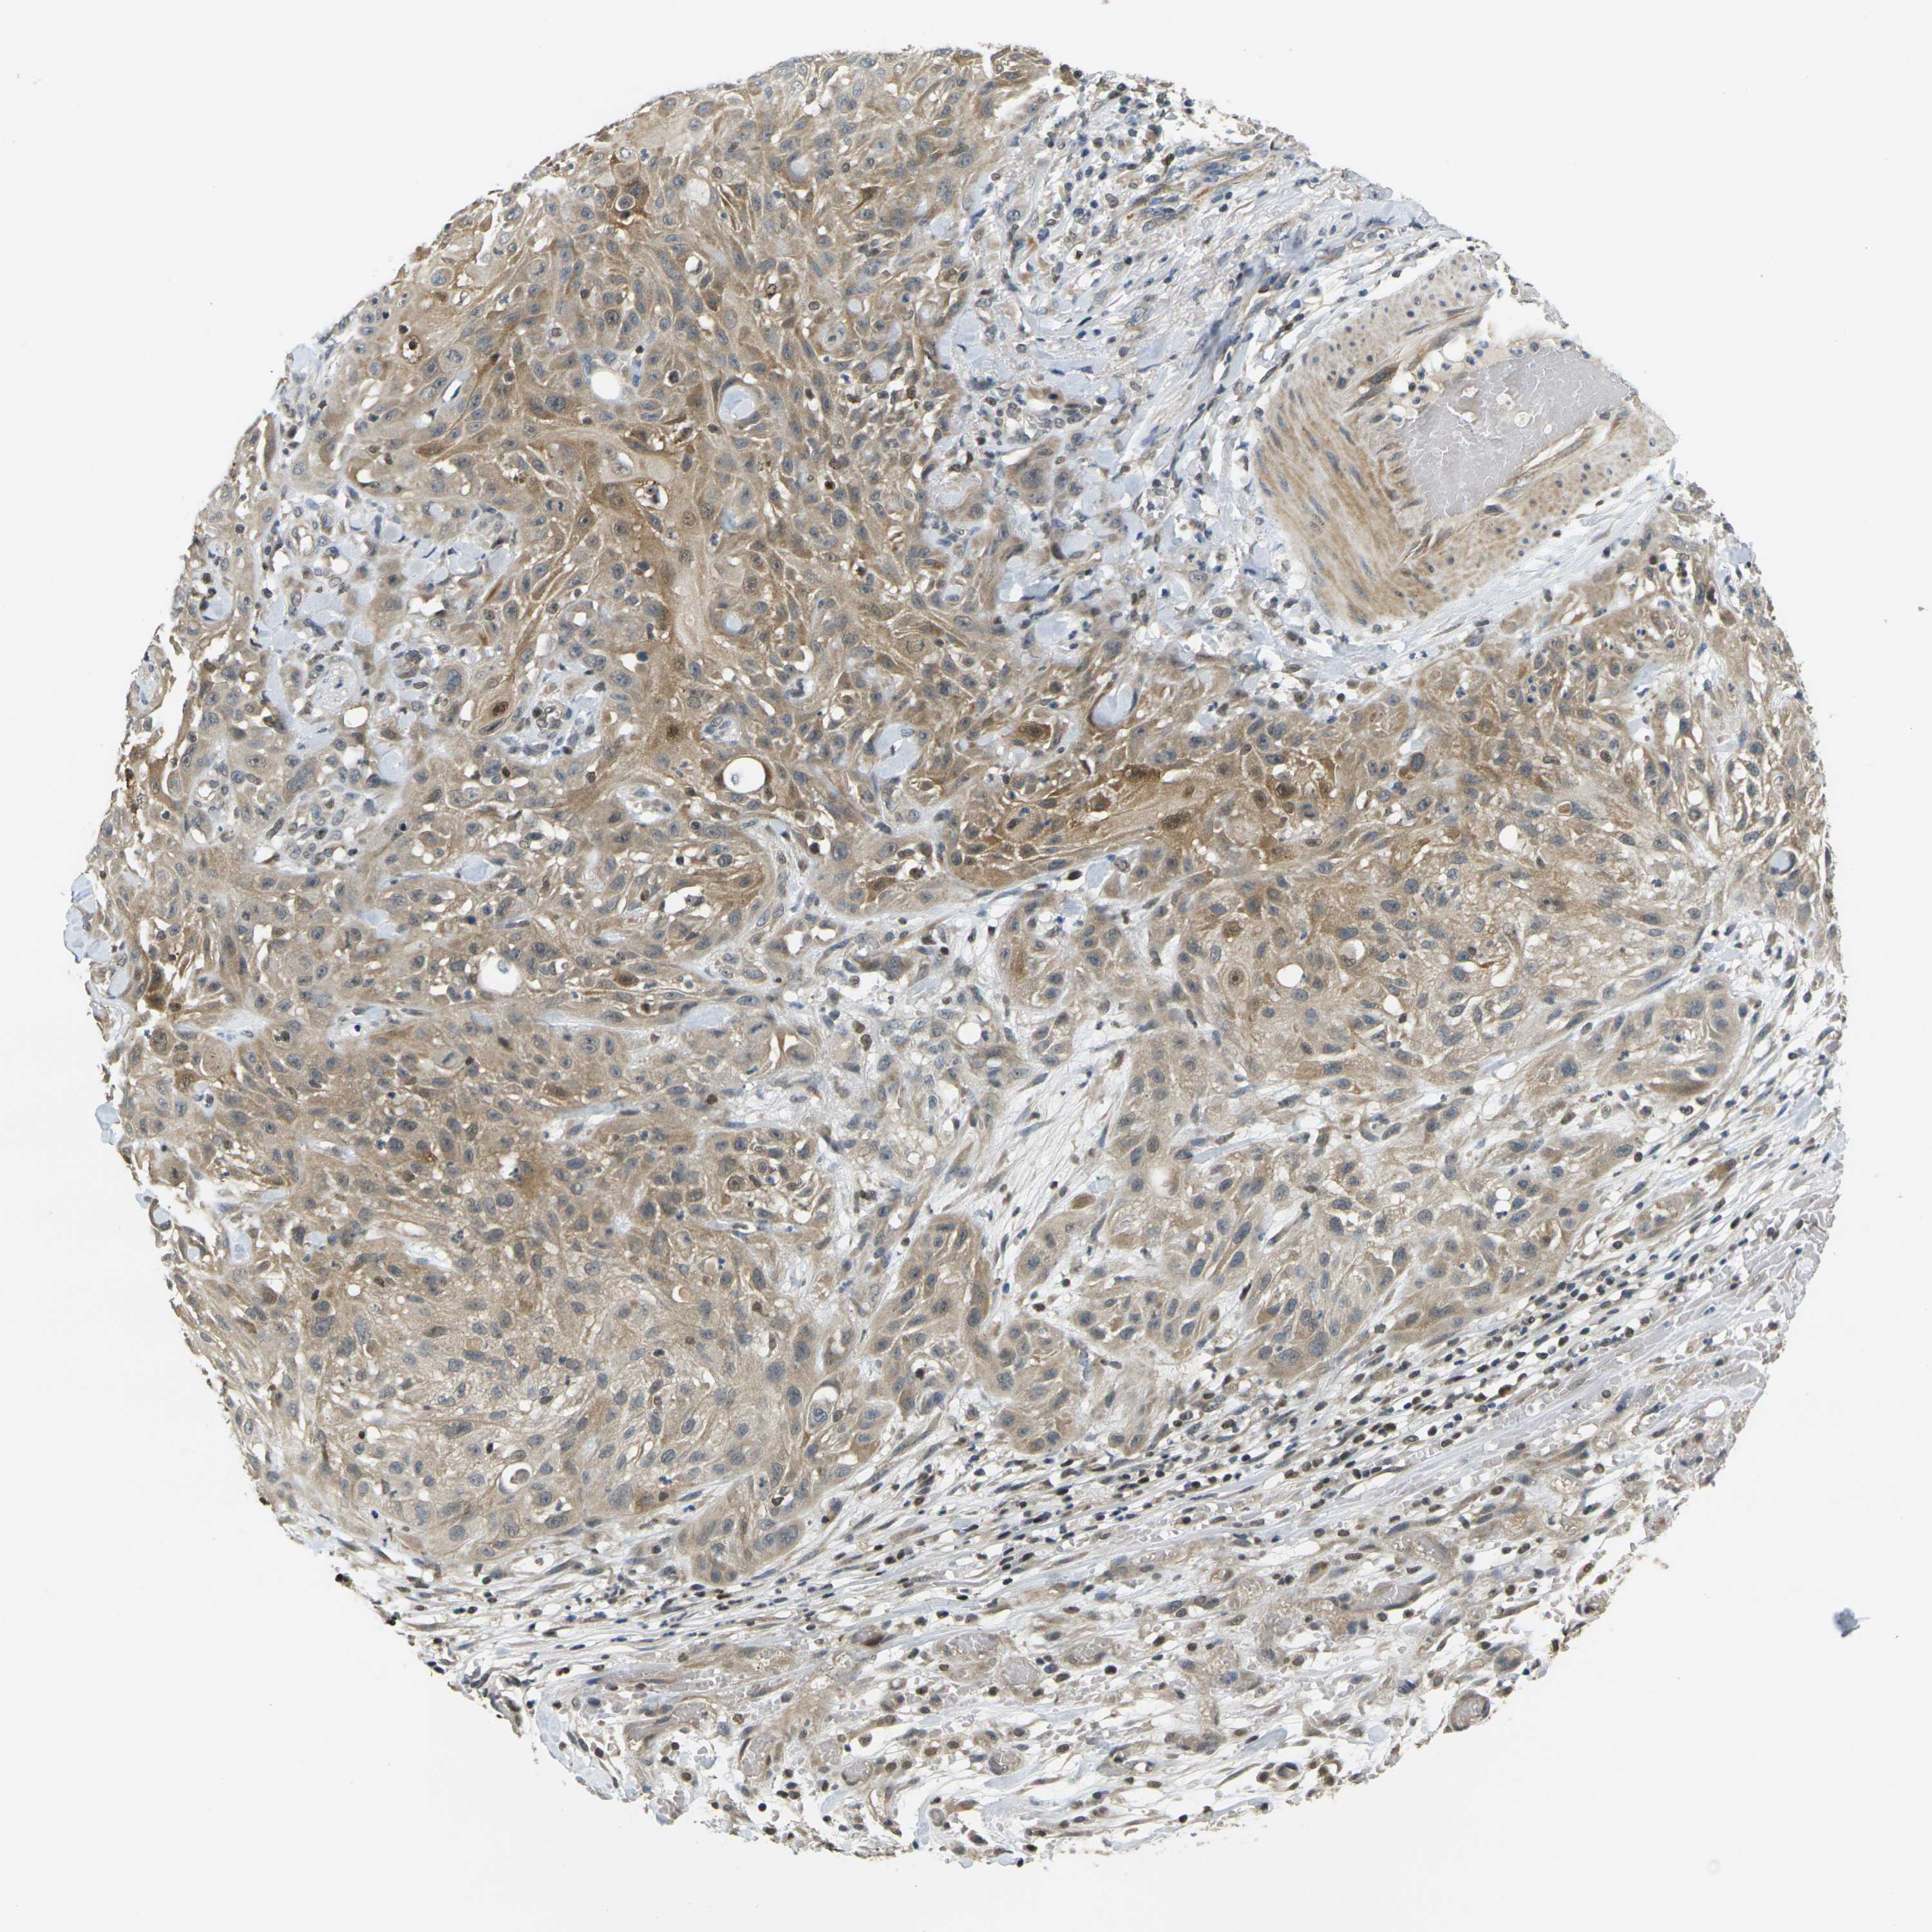

SKIN CANCER - Protein expressioni

A mouse-over function shows sample information and annotation data. Click on an image to view it in a full screen mode. Samples can be filtered based on level of antibody staining by selecting one or several of the following categories: high, medium, low and not detected. The assay and annotation is described here.

Each image is clickable and will lead to virtual microscopy that enables deeper exploration of all samples and also displays staining intensity scores, fraction scores and subcellular localization as well as patient and tissue information for each sample.

Antibody HPA017762

Squamous cell carcinoma, NOS